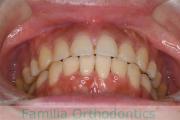

下の前歯が後ろにあるのが気になるとのことで来院されました。非抜歯で行うことも可能でしたが、上下左右から小臼歯抜歯をして治療を行うことをご希望になりました。

マルチブラケット法にて治療を行い、約3年、40回の通院が要でした。

かみ合わせが深い(上の前歯で下の前歯が覆われてしまう)ので、保定をしっかりしないと、また深くなってきてしまいやすいです。

前歯の関係など